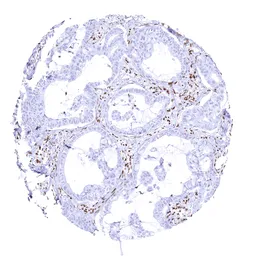

Anti-BRG1 antibody [MSVA-397R] HistoMAX™ used in IHC (Paraffin sections) (IHC-P). GTX04486

GTX04486 IHC-P Image

IHC-P analysis of human pulmonary adenocarcinoma tissue using GTX04486 BRG1 antibody [MSVA-397R] HistoMAX™.

Pulmonary adenocarcinoma with complete loss of BRG1 staining of tumor cells.